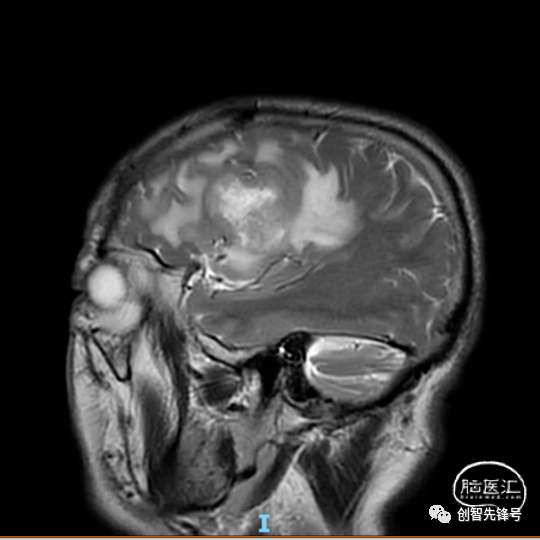

患者自述半年余前无明显诱因下出现言语不清,伴全身乏力,头颅CT提示:右侧额叶占位,性质待定。MR平扫+DWI+增强扫描+MRS提示:右额叶脑胶质母细胞瘤。既往有高血压病史3年,具体不详,血压控制不佳。有糖尿病病史,未治疗,血糖控制不佳。

术前检查:左侧额叶占位,考虑肿瘤性病变,高级别胶质瘤可能性大,粘连邻近脑膜。